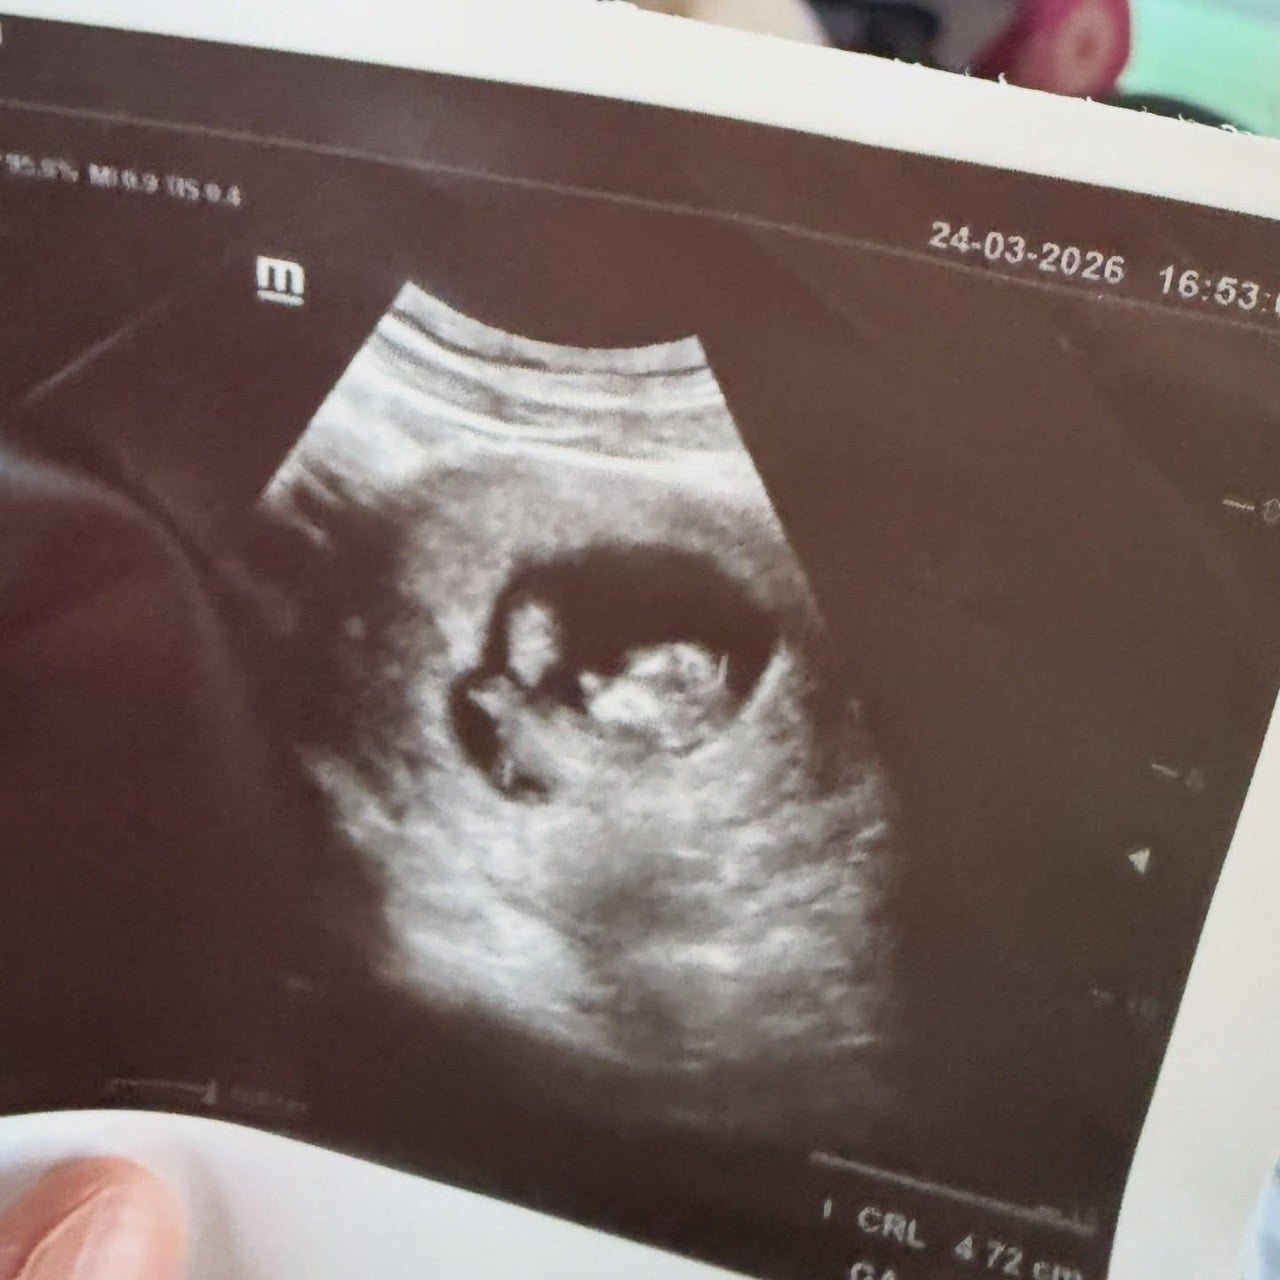

โดยล่าสุด (6 เมษายน) ฟีฟ่าได้โพสต์ภาพอัลตราซาวด์ผ่านอินสตาแกรมส่วนตัว พร้อมข้อความสุดอบอุ่นว่า “มาชาอัลลอฮ์ ตะบารอกัลลอฮ์ หมายความว่า นั่นคือพระประสงค์ของอัลลอฮ์ ขออัลลอฮ์ทรงให้กำเนิดอย่างราบรื่น Alhamdulillah”